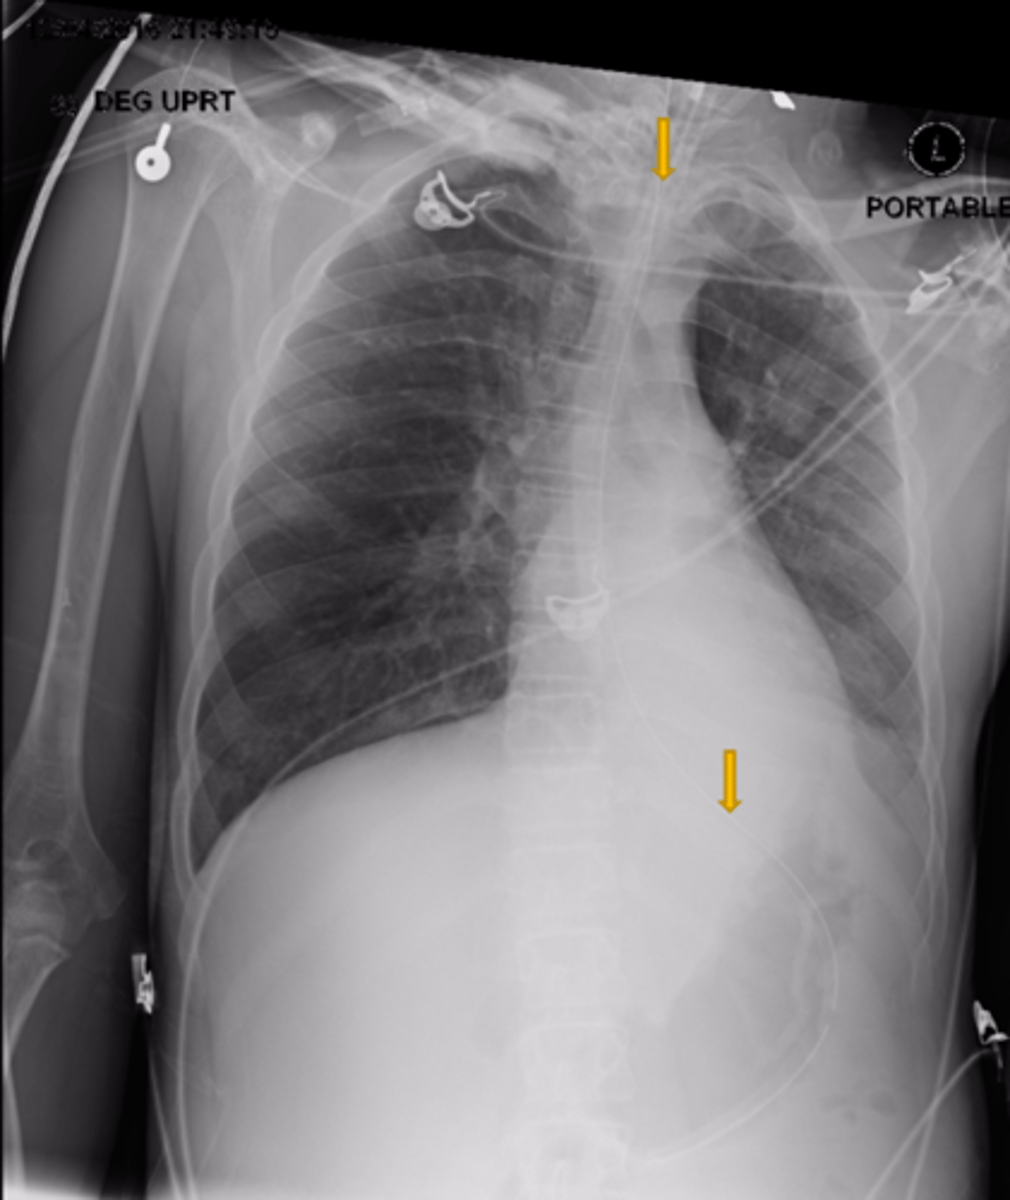

What is the structure the yellow arrows are pointing at?

Is this a high-quality film?

Left lung

Where is the abnormality located in the chest?

Atelectasis

What is the red arrow indicating?

Effusion

What is the likely interpretation?